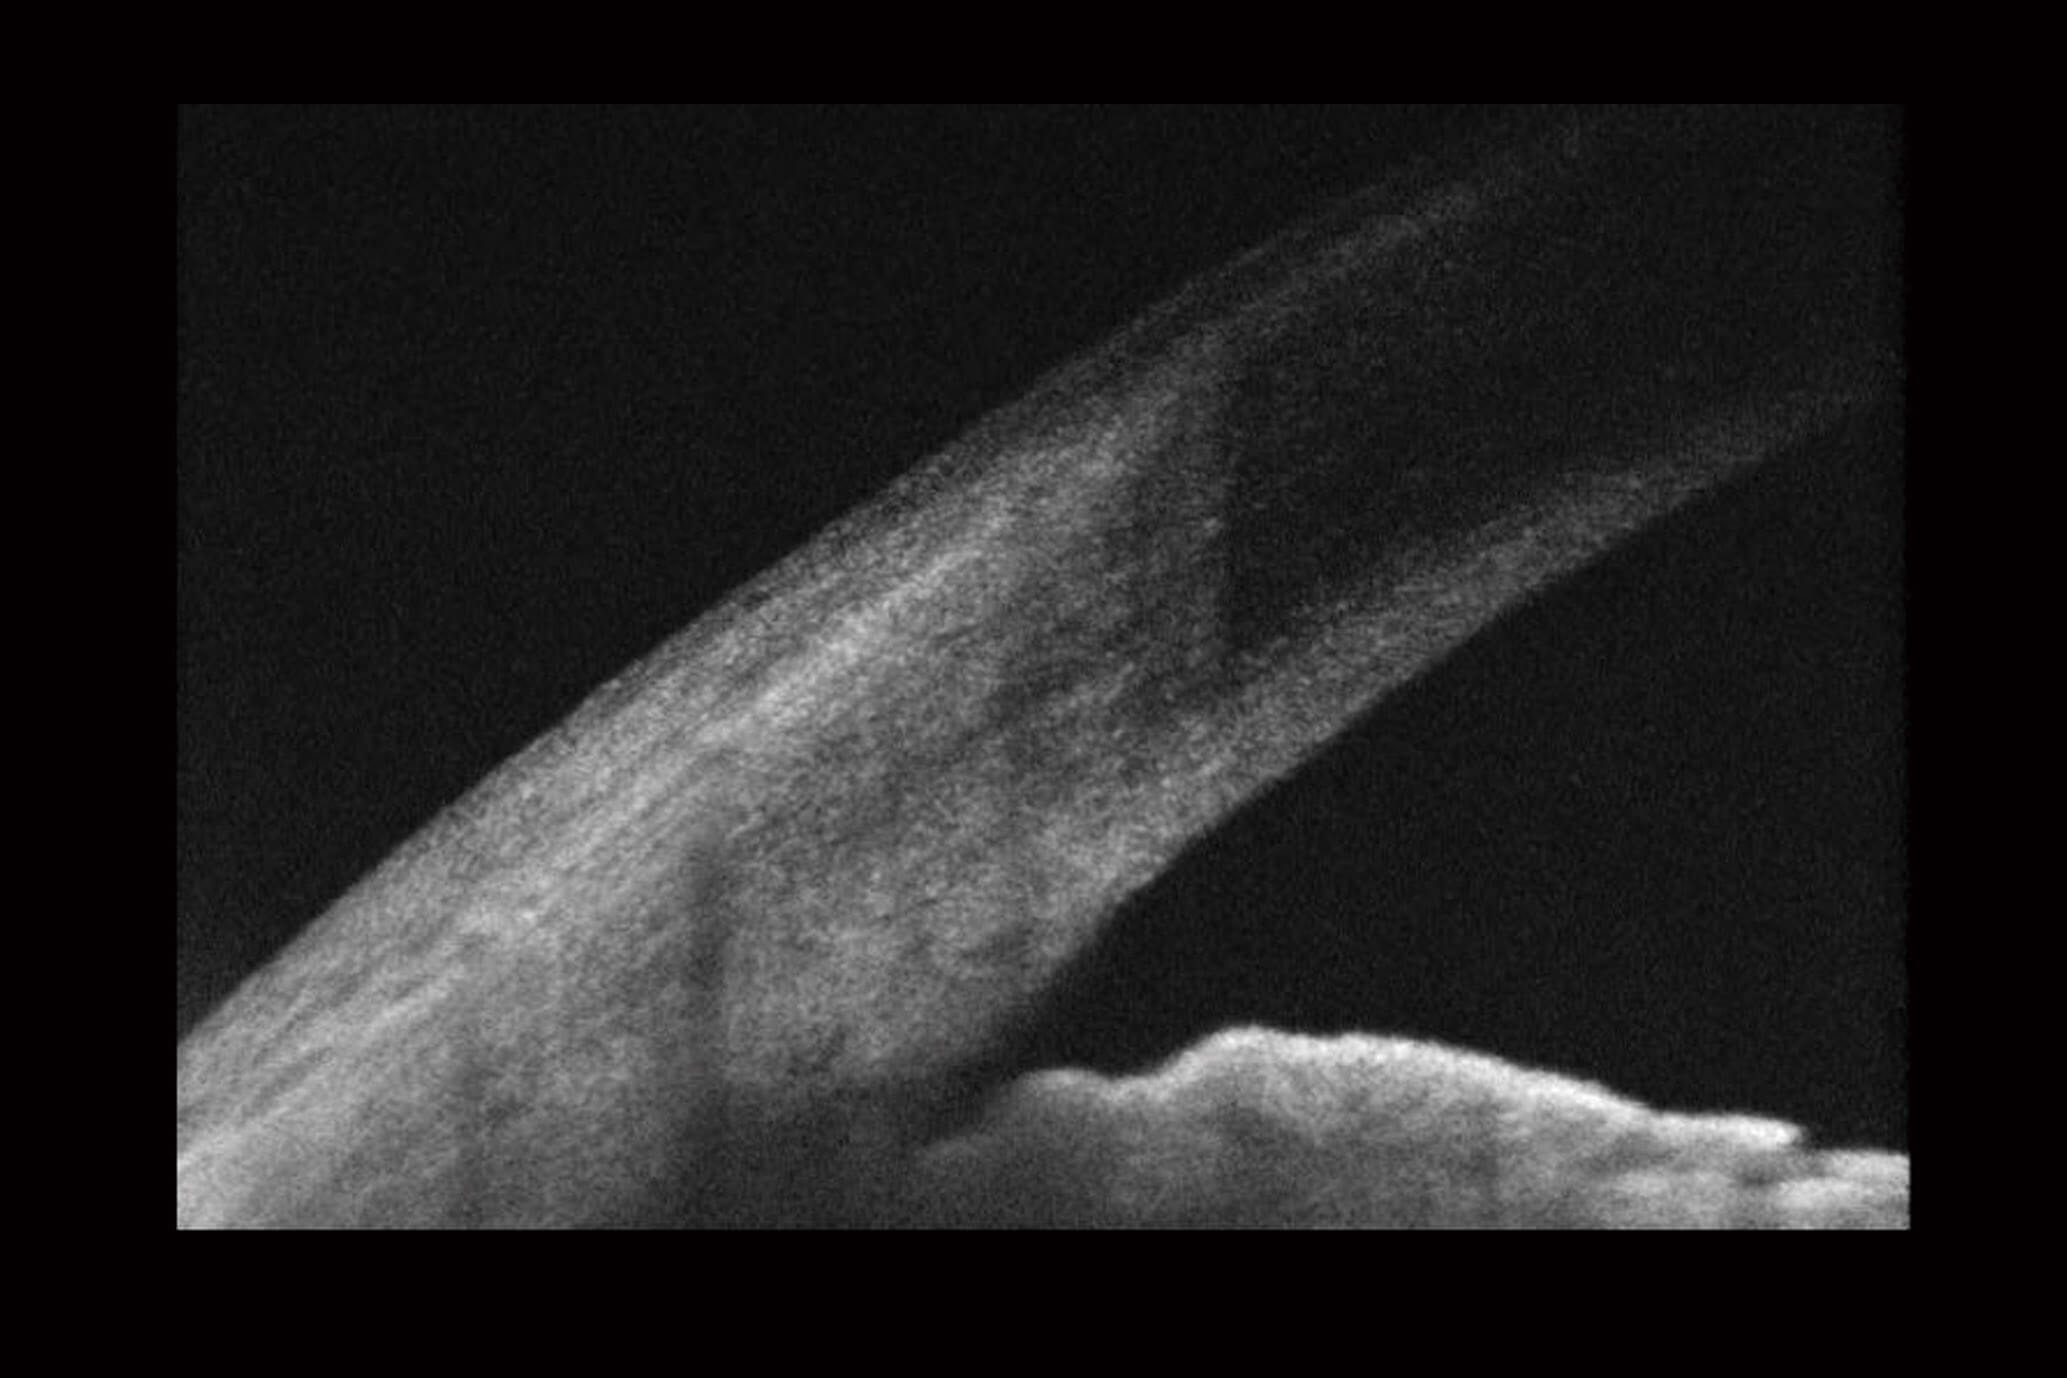

Optical Coherence Tomography (OCT) is an advanced eye scan, similar to ultrasound. The OCT uses light rather than sound waves to illustrate the different layers that make up the back of the eye. Within 2 seconds, the OCT takes over 30,000 individual scans of the back of the eye and this is used to produce a 3D image of the retina and optic nerve. The scan gives an accurate cross-sectional map through the retina and allows examination of the back of the eye in incredibly fine detail.

The OCT also captures a digital photograph of the surface of the eye at the same time, and this can then be cross-referenced with any areas of concern.

The scan shows us beneath the surface of your retina, so we can see and better understand the very fine changes which can be indications of something unhealthy or abnormal.